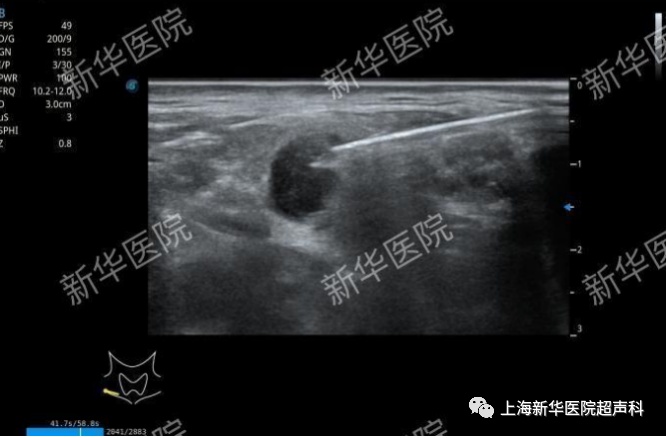

(4)超声引导细针穿刺抽吸细胞学检查(FNA):甲状腺结节或颈部近锁骨上等危险部位的淋巴结,可行FNA穿刺及病理检查明确良恶性。

右侧锁骨上淋巴结穿刺活检